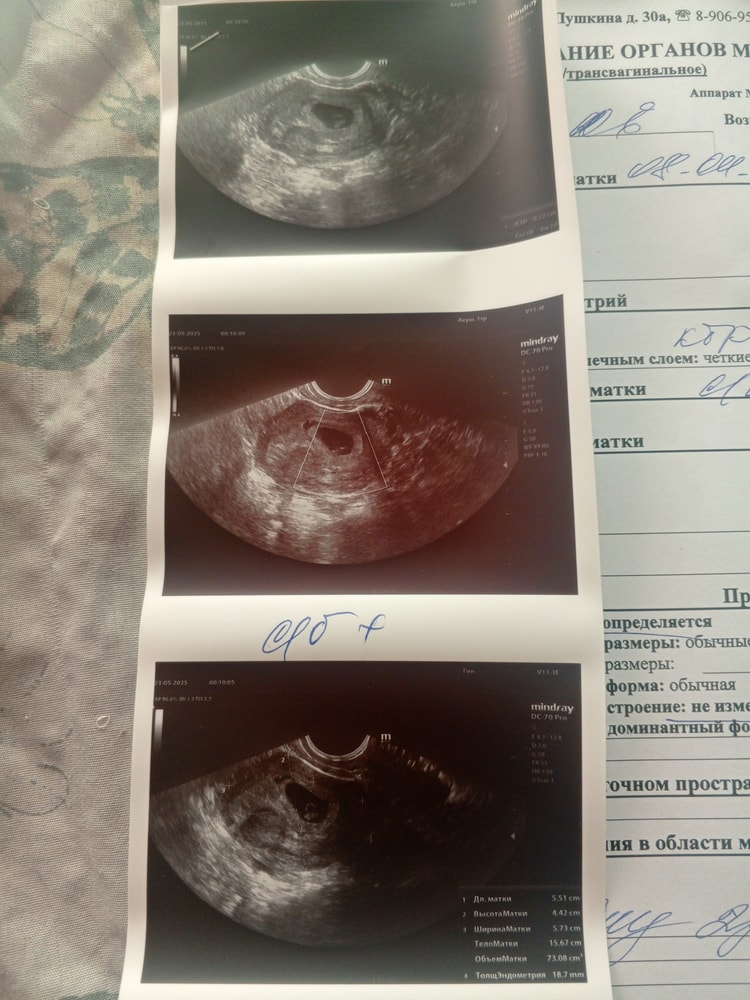

Вчера еще ходила на узи, увидела свою кроху, на узи сказали что на примерно 3 недельке была отслойка организм пытался отторгнуть, но сказали переживать не стоит, сейчас угрозы никакой нету, но почему выделения то с кровью пошли?

Фото с узи

На фото видно что была отслойка